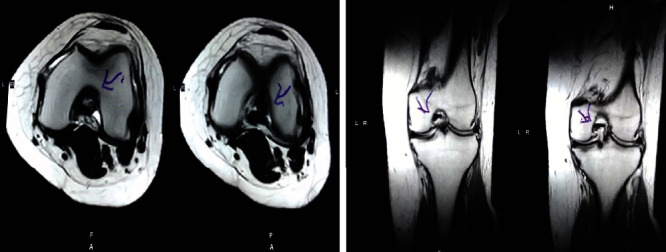

治療后一個月進(jìn)行隨訪。在第一次細(xì)胞治療后,患者的疼痛明顯減輕。第二次療程后,她沒有疼痛,并注意到運(yùn)動范圍有所改善。持續(xù)的物理治療也觀察到下肢肌肉力量的增加。從治療開始(11個月前)到最后一次隨訪(4個月前),患者按照建議的飲食和基于運(yùn)動的方案減重了11公斤。因此,她現(xiàn)在整體身體健康,能夠更舒適地進(jìn)行日常生活活動。表3顯示治療前后的MRI檢查結(jié)果。人物的圖1和的和圖2顯示半月板撕裂的治療前和治療后(1年后)圖片。觀察到損傷程度的改善圖2。